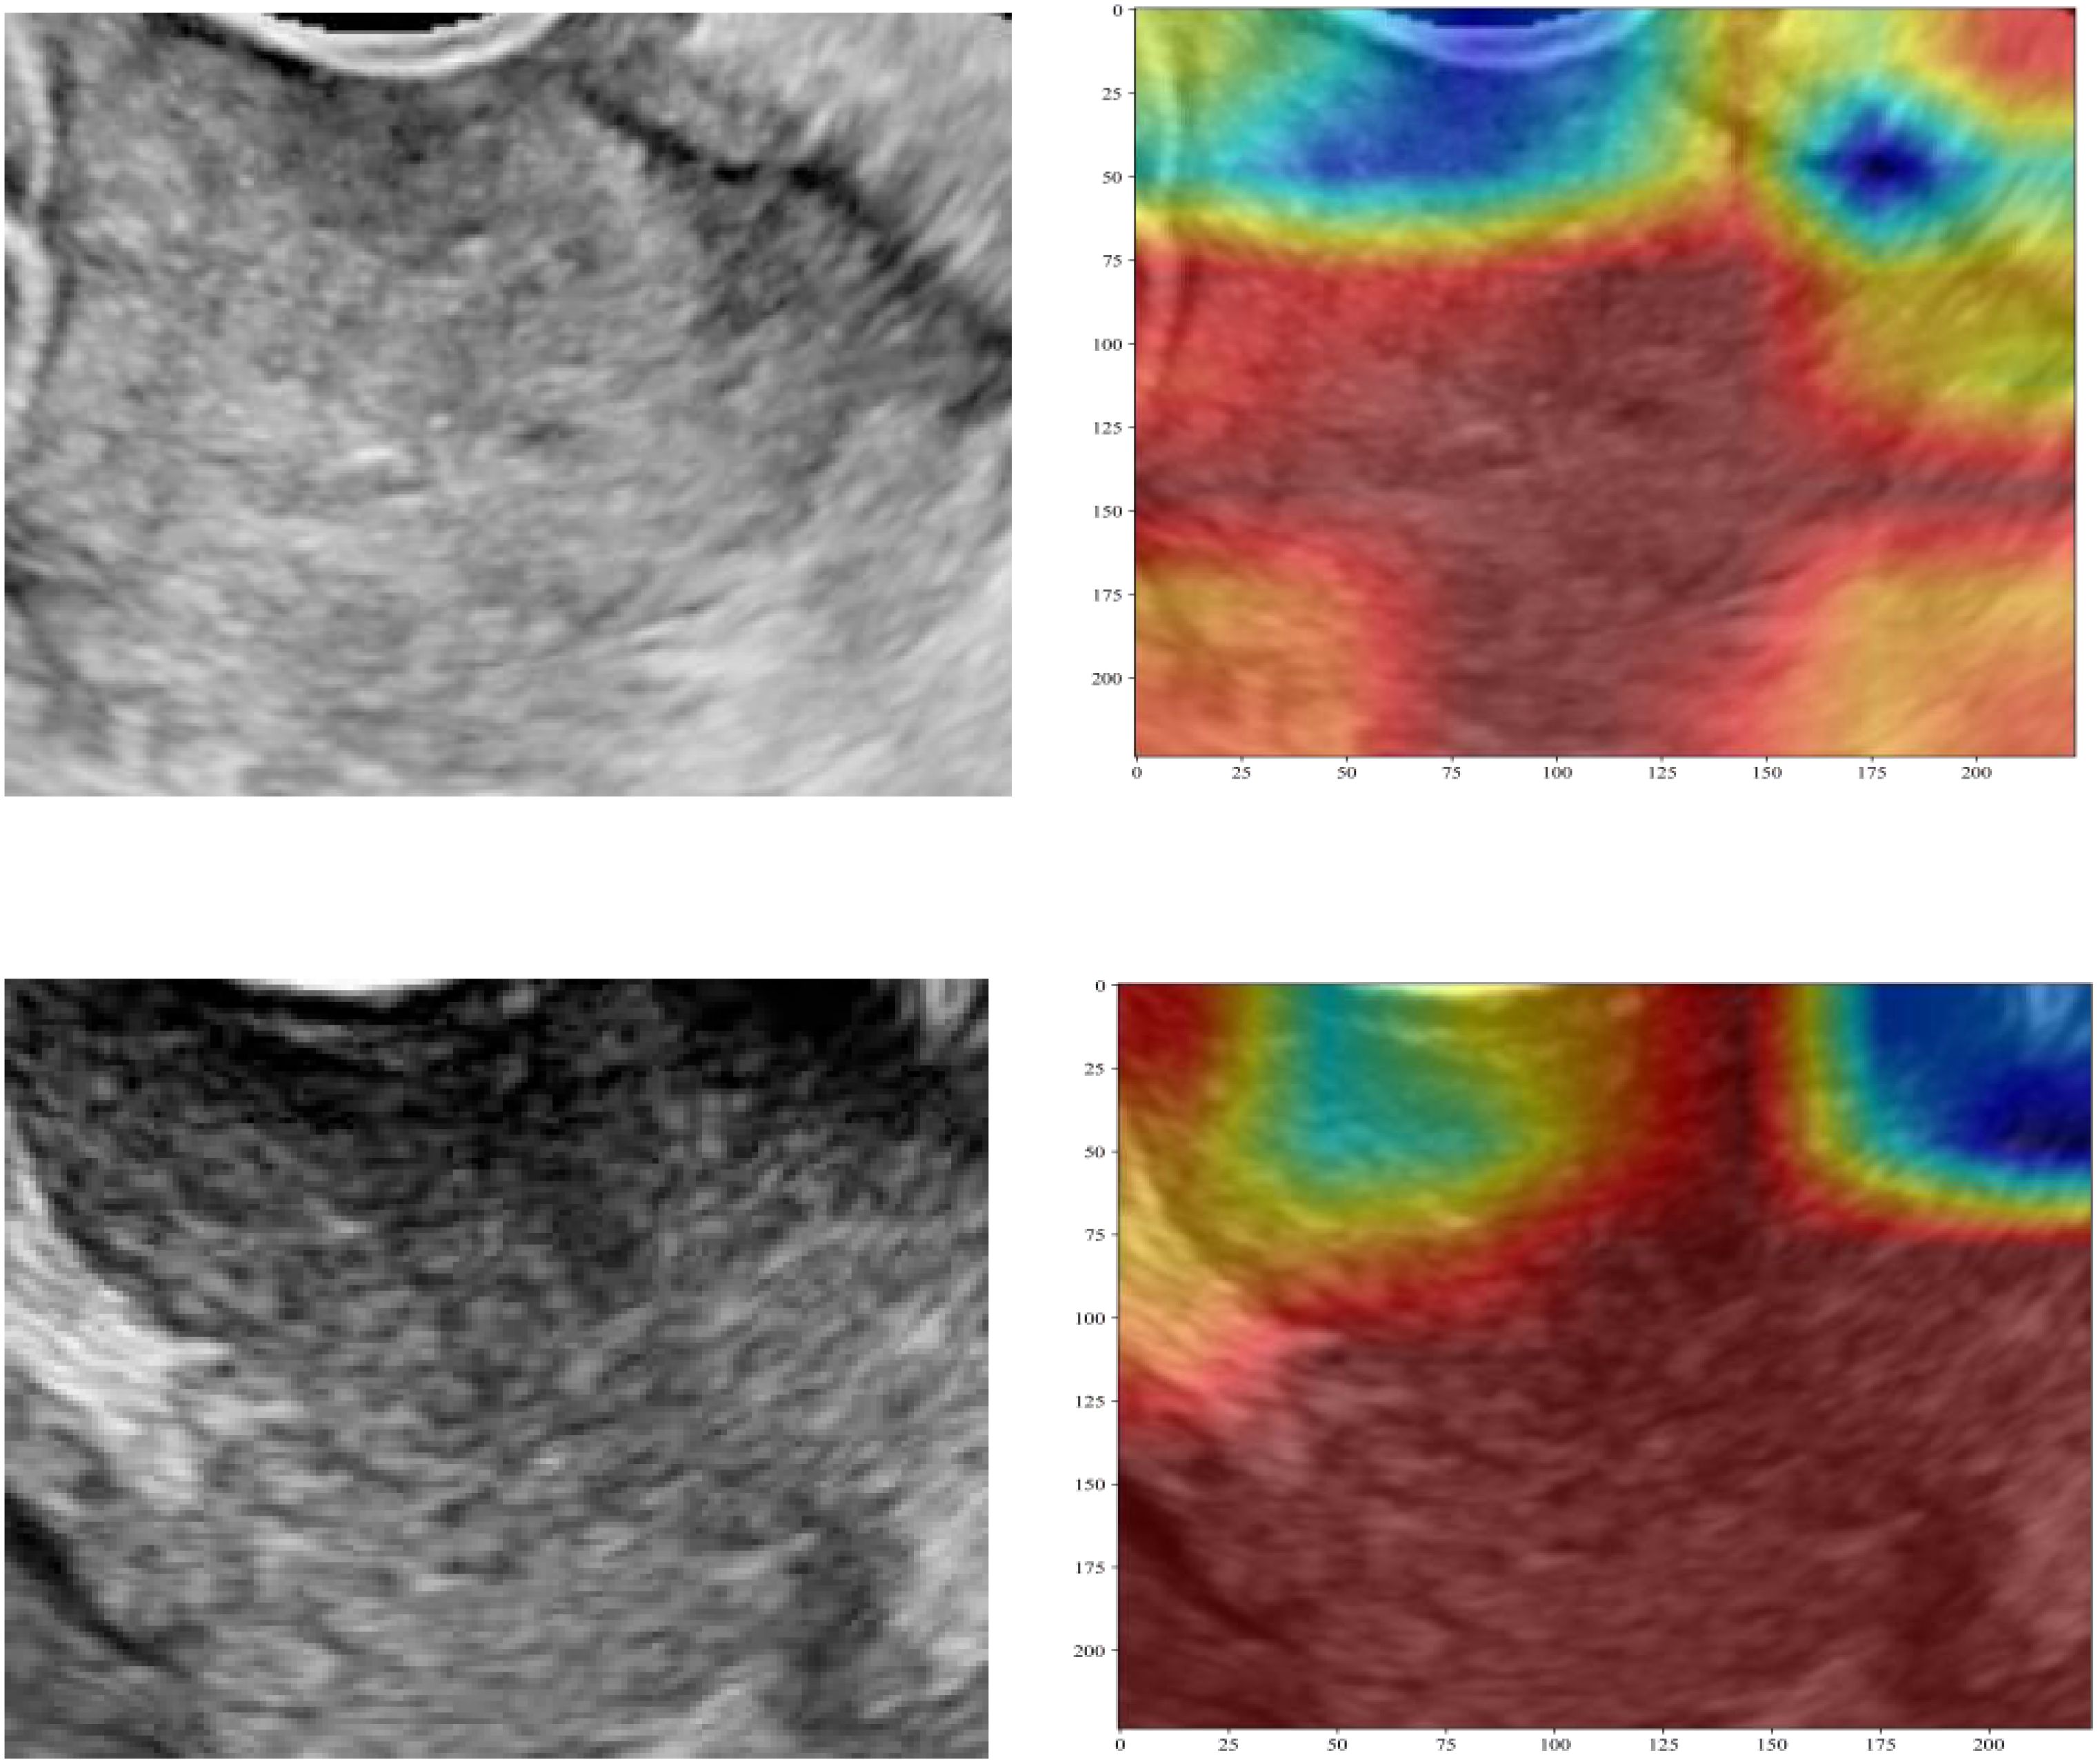

Background: To develop and validate a multimodal fusion model integrating ultrasound-based radiomics, deep transfer learning (DTL), and clinical parameters for preoperative pelvic lymph node metastasis (PLNM) prediction in cervical cancer. Methods: A retrospective cohort of 421 patients with surgically confirmed cervical cancer was divided into the training (70%, n = 294) and testing (30%, n = 127) sets. Ultrasound-based radiomics (1,561 handcrafted features) and 3 DTL architectures (DenseNet121, ResNet50, AlexNet) were employed for feature extraction. After redundancy reduction (Spearman correlation, least absolute shrinkage and selection operator regression) and principal component analysis, fused radiomics-DTL features were combined with clinical predictors. Eight machine learning classifiers were evaluated, and the optimal model was used to construct a nomogram. Performance was assessed using area under the curve (AUC), calibration curves, and decision curve analysis (DCA). Results: The multilayer perceptron-based fusion model achieved a testing AUC of 0.753 , outperforming standalone radiomics (AUC = 0.729) and DTL models (best AUC = 0.702; DenseNet121). Integration of clinical predictors (maximum tumor diameter and red blood cell count) further enhanced performance, yielding a nomogram with training/testing AUCs of 0.871 and 0.764, and a testing sensitivity and specificity of 58.1% and 84.4%,respectively. DCA demonstrated superior clinical utility for the nomogram across threshold probabilities (10%–50%). Conclusions: We developed a multimodal fusion model integrating ultrasound-based radiomics, DTL, and clinical parameters for preoperative PLNM prediction in cervical cancer.The proposed nomogram provides a clinically applicable, cost-effective tool for preoperative PLNM prediction, particularly valuable for optimizing treatment decisions in resource-limited settings.